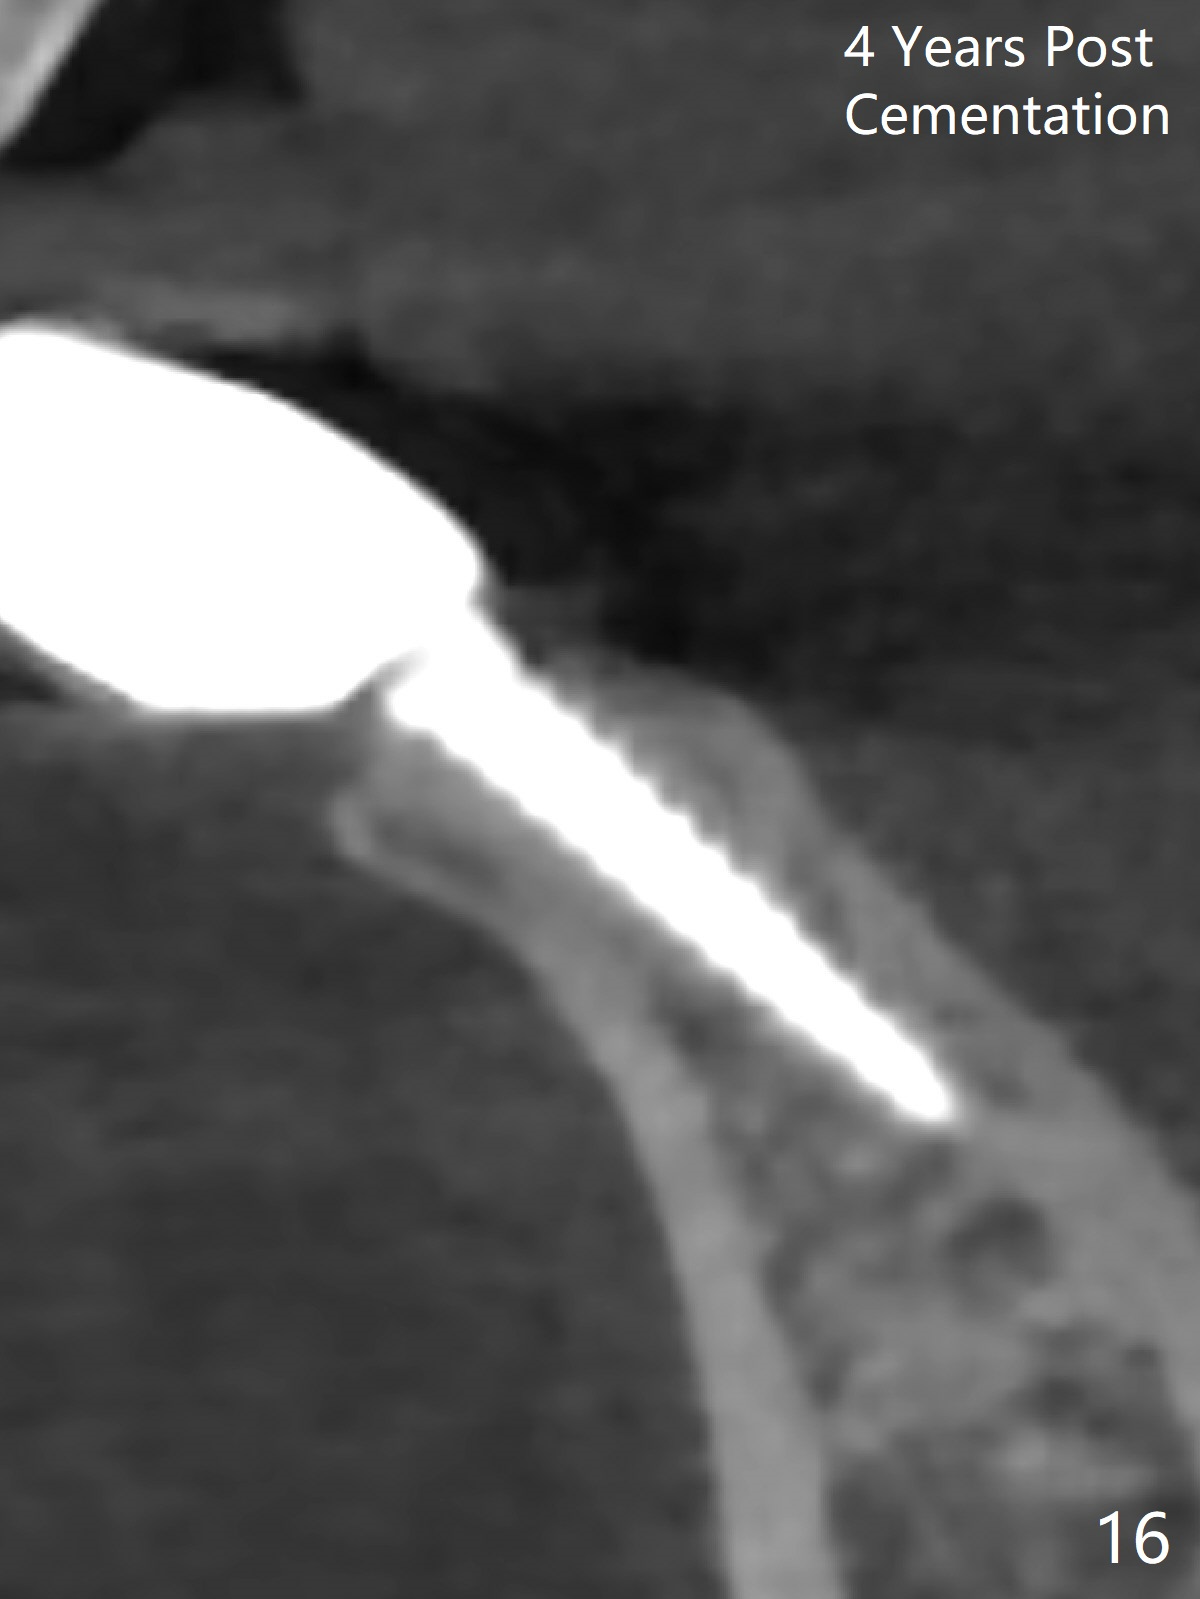

Fig.10,11 show 7 day follow up.  The permanent crown is seated 4.5 months postop (Fig.12).  Minimal bone resorption occurs at the crest 4 months postop (Fig.13), which is most likely associated with conservative approach (flapless).  The patient returns for follow up 2.5 months post cementation (Fig.14,15).  The implant remains in the bone 4 years post cementation (Fig.16 CT coronal section; lingual thread exposure, corresponding to preop defect in Fig.1).   There is mild coronal bone resorption 5 years 4 months post cementation (Fig.17).